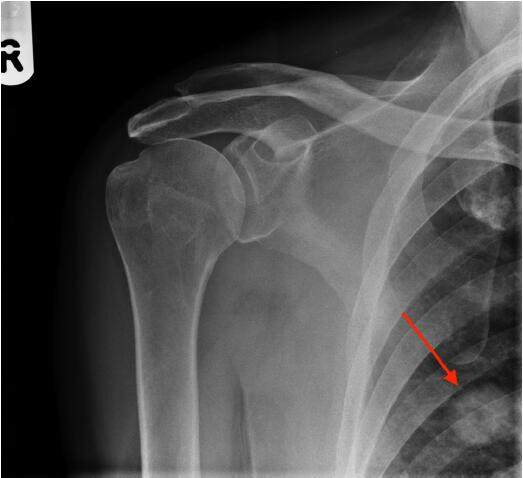

患者,男性,62歲,跌倒后,肩膀越來越疼。全科醫(yī)生要求該患者進(jìn)行放射檢查(圖1)。

圖1右肩前位X光平片

圖2肩X光片顯示一空洞性肺結(jié)節(jié),約2cm。很可能是原發(fā)性肺癌,需要轉(zhuǎn)診至肺癌多學(xué)科小組。

圖2右肩前位X光平片,紅色箭頭指示一空洞性肺結(jié)節(jié)

該例患者接受了胸部和腹部CT掃描,隨后取了活檢,證實(shí)為T2N0M0原發(fā)性肺腺癌。對(duì)給患者予以手術(shù)切除,2年隨訪時(shí)仍無病。